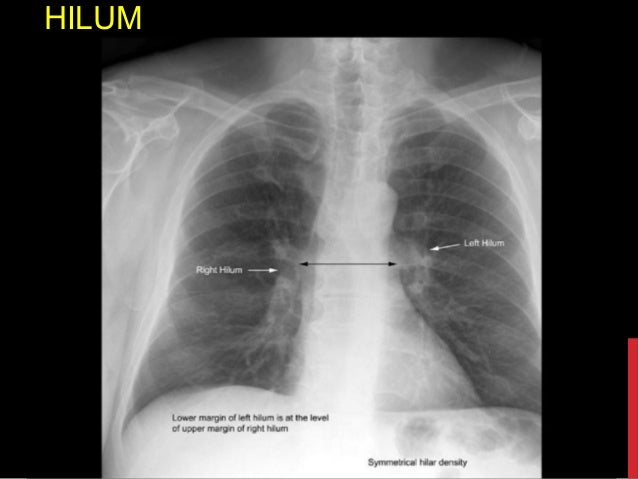

How To Interpret A Chest X-ray (lesson 10 - Self

Source: www.slideshare.net Chest X-ray Interpretation - Ppt Video Online Download

Source: www.slideshare.net Chest Radiograph

Source: emedicine.medscape.com Chest X-ray Review. - Ppt Video Online Download